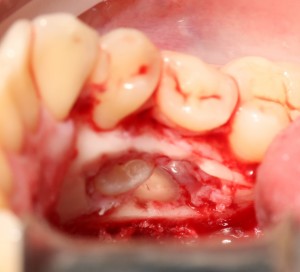

Теоретически, лунки можно чем-нибудь заполнить. Только чем? И для чего?

Костная ткань сама регенерирует, если ей не мешать. Поэтому не стоит толкать в лунки какой-нибудь остеопластический материал, типа Cerabone или Bioss. Нет смысла.

В данном случае я использовал обычную коллагеновую губку — и то, только для того, чтобы «костная дверца», которую я выпилил в самом начале операции, не провалилась внутрь:

Теперь запиливаем «костную дверцу» на ее законное место:

И накладываем швы.